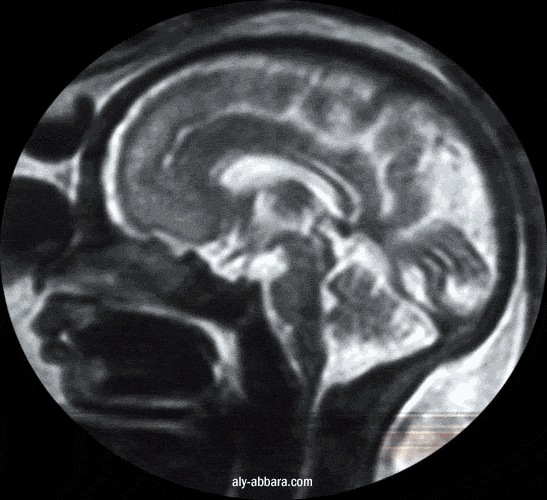

Coupe sagittale médiane par IRM du cerveau fœtal à 32 SA

On met en évidence le corps calleux, le 3e et 4e ventricules, le cervelet, le tronc cérébral

et le cortex de la face interne de l'hémisphère cérébrale

Comparer cet aspect à l'aspect du cortex cérébral à 39 SA où on peut mettre en évidence les circonvolutions cérébrales

Coupe montrant le corps calleux